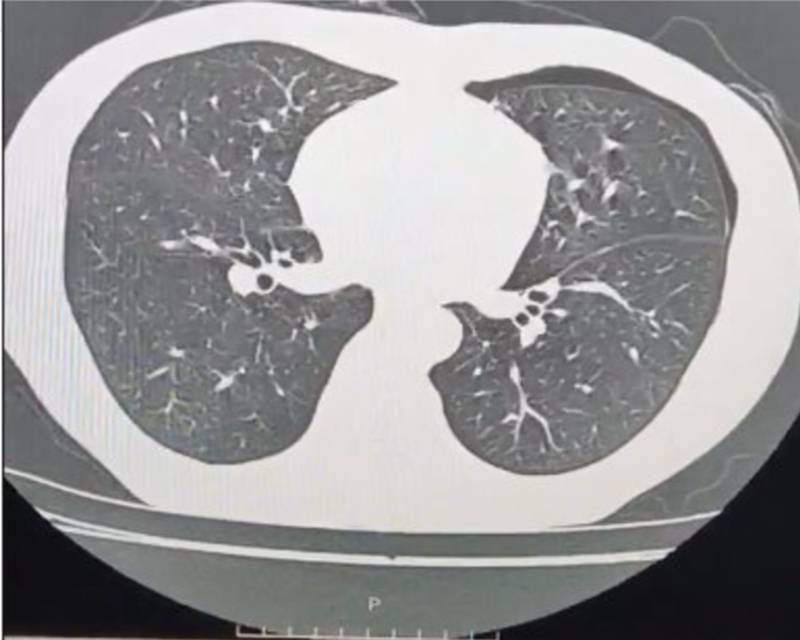

Hình ảnh chụp cắt lớp vi tính phổi liều thấp ghi nhận tràn khí khoang màng phổi trái mức độ nhiều

Kết quả chụp cắt lớp vi tính phổi liều thấp ghi nhận: hình ảnh tràn khí khoang màng phổi trái mức độ nhiều, gây xẹp thụ động nhu mô phổi (khoảng 75%), nghĩ đến do vỡ kén khí; kén khí thùy trên phổi trái; giãn phế nang cạnh vách thùy trên hai phổi.